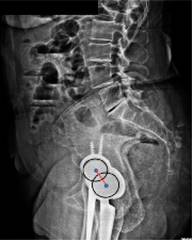

Es oportuno abrir aquí un paréntesis para definir qué es el «eje bicoxofemoral». Debido a que en una radiografía lateral es muy difícil hacer coincidir los centros de rotación de ambas cabezas femorales, se utiliza el concepto de «eje bicoxofemoral». Este eje se localiza en la parte media de una línea trazada entre los centros de rotación de ambas cabezas femorales en una radiografía lateral espino-pélvica (Figura 17).

Figura 17: El «eje bicoxofemoral» se localiza en la parte media de una línea trazada entre los centros de rotación de ambas cabezas femorales en una radiografía lateral espino-pélvica.